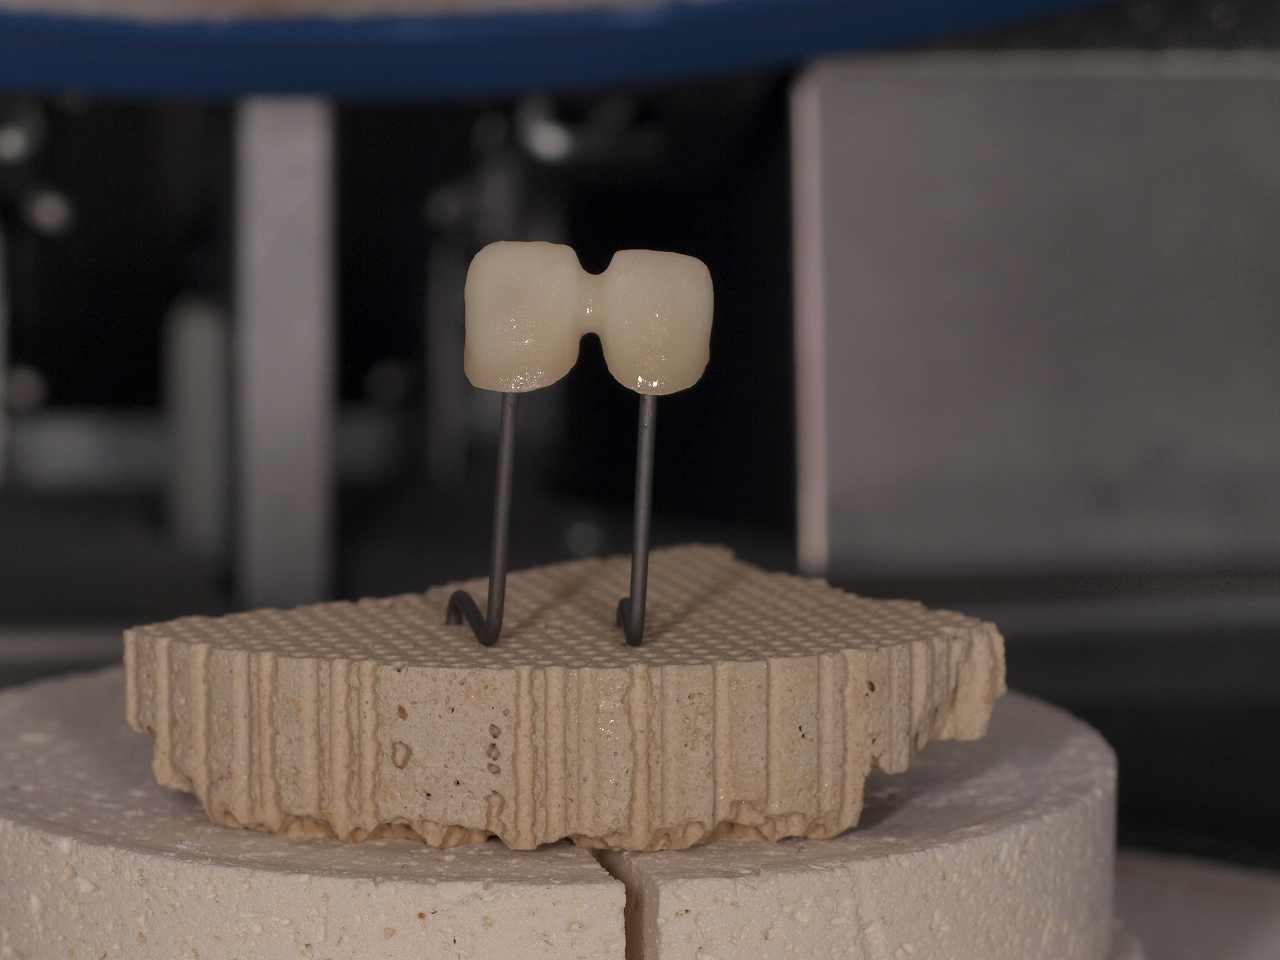

設計後、連冠にてフレームを作成していきます

9時間シンタリングを行い基礎となるジルコニアフレームを作成

模型上にて適合を見ていきます